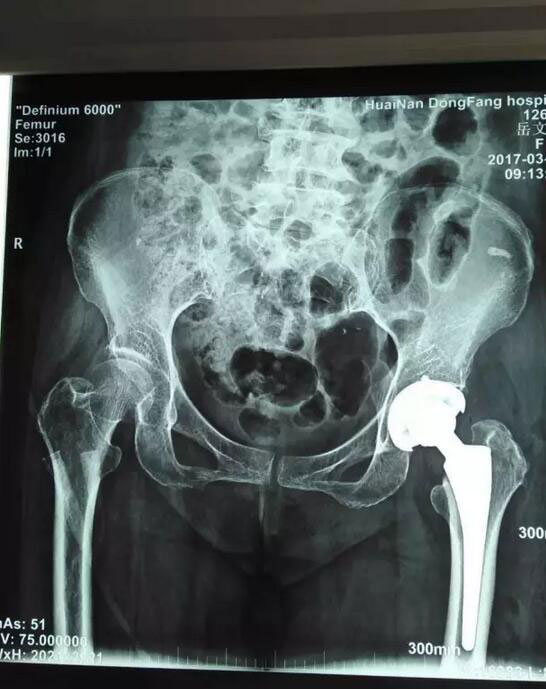

术前术后对比

岳老太太今年已经70岁,因为股骨颈骨折,需要进行全髋关节置换手术。经过总院骨科团队慎重研究并向老太太家属沟通后,3月6日接受了这一最新理念的手术,也是总院骨科开展的第二此类手术。手术由鲁木主任亲自主持,顺利结束后老人安全返回病房。术后第二天,老太太就可以下床并自如行走、弯腰,甚至可以自己穿上袜子,岳老太太的老伴对此惊喜不已,连连对鲁木主任和医护人员们表示感谢。在他的印象中,动了这么大的一个手术,最少要在床上躺上十天半个月,没想到现在恢复的这么快,这么好!一周后,老人恢复良好,顺利出院。

“尚氏切口”又名侧位直接前路切口,是一种应用普通关节置换器械而直接前路治疗髋关节疾病的微创手术方法,优点是通过肌间隙直接进入关节,对病人组织结构干扰少,病人可以很快恢复正常功能,是当今骨科界公认的微创关节置换技术,目前国内乃至世界的骨科医生都在研究和应用该技术。

鲁木主任介绍说:以前的髋关节置换手术都是从臀后切口,医学上称为“后侧入路”,这种术式要切断“外旋肌群”,术后会导致髋关节后外侧稳定性降低,虽然操作起来相对简单方便,但术后的功能恢复相对延迟。术后一个月内,病人还要在两腿间夹着一个枕垫,以防止双腿做内收动作后新置换的髋关节脱落。而新的“尚氏切口”则完全避免了这个风险。